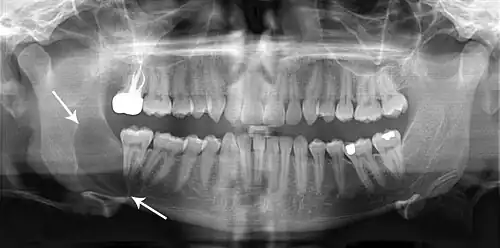

Large odontogenic keratocyst with impacted wisdom teeth superficial to lesion

As the condition is quite rare, opinions among experts about how to treat OKCs differ. A 2015 Cochrane review found that there is currently no high quality evidence to suggest the effectiveness of specific treatments for the treatment of odontogenic keratocysts.[8] A more recent review from 2017 found that the rate of recurrence varies significantly according to some clinical, radiographic, and histopathological features, as well as surgical management.[16] Treatment depends on extent of multilocularity and cyst. Small multilocular and unilocular cysts can be treated more conservatively through enucleation and curretage. Treatment options for KTOC may vary according to its size, extent, site, and adjacent structures.